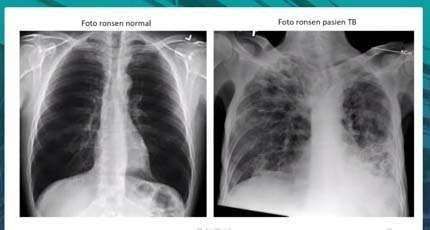

Ia menambahkan, keterbatasan alat juga menjadi tantangan pelayanan di wilayah kerjanya. “Karena alatnya tidak tersedia di seluruh puskesmas di Belu, hanya ada beberapa puskesmas yang sudah punya alat yang namanya TCM. Kemudian apabila hasilnya negatif, kita juga masih lanjutkan lagi dengan pemeriksaan rontgen,” katanya.